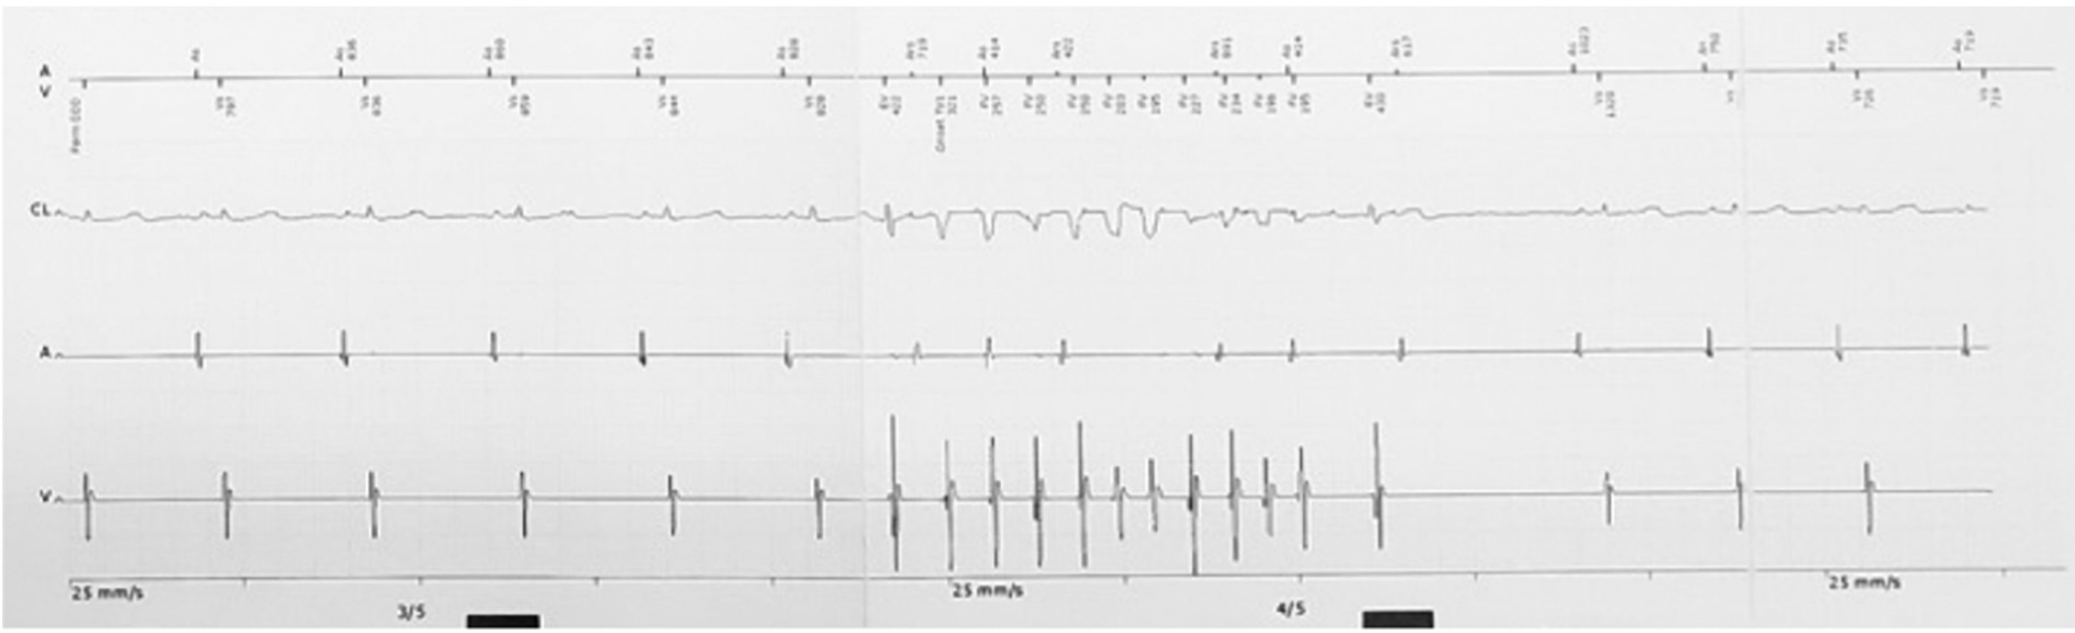

然而,故事并沒有這么簡單,入院后室早才一步步顯露出它的真面目。這次發作的室早與入院時明顯不同,聯律間期縮短至300ms,出現在T波頂峰,室早后誘發了尖端扭轉型室速(TdP),室速發作時患者同時出現了暈厥發作。此后,患者又出現了多次TdP發作,且發作時間越來越長,最終演變成室顫,體外除顫后才恢復正常竇律。

3.png

圖3 短聯律間期室早誘發尖端扭轉型室速